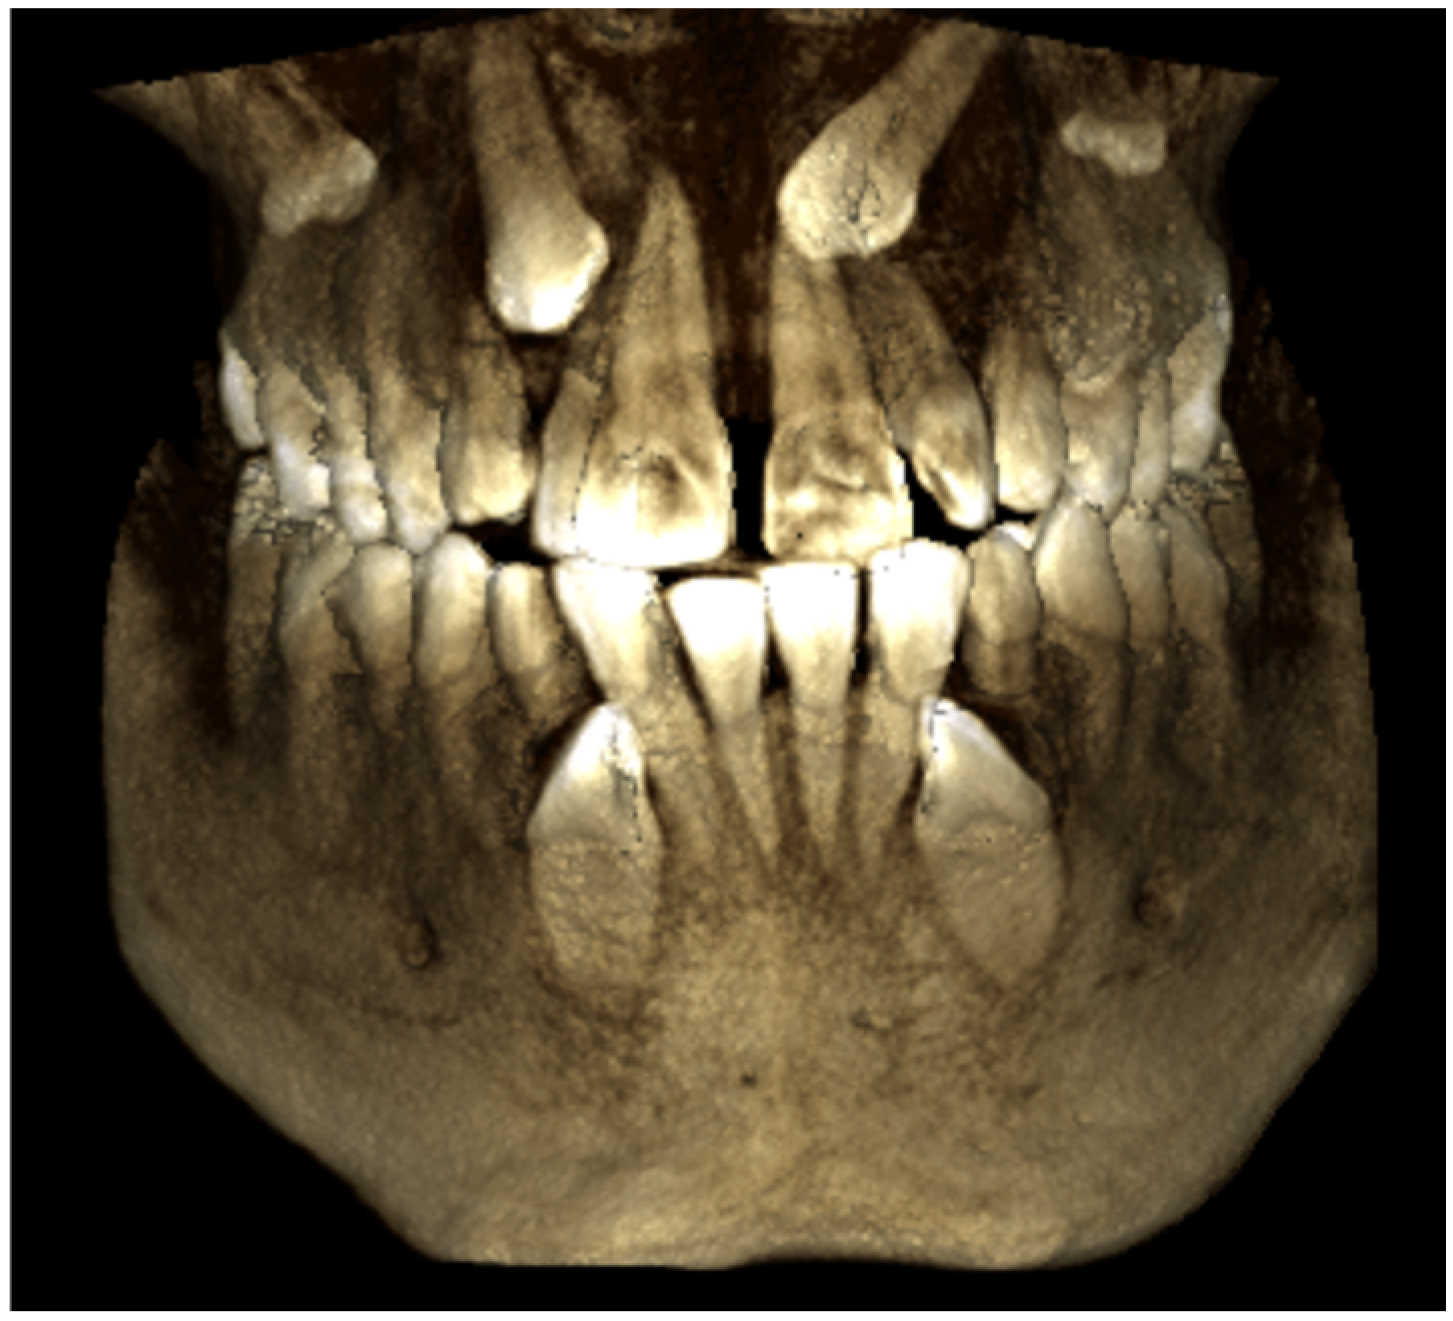

Two-Dimensional Radiographic Diagnosis of Maxillary Canine Impactions

2.2. Data Collection

2.3. Data Analysis